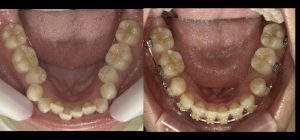

矯正治療前と開始後1年経過時の比較です。

抜歯したスペースを閉じながら、歯の並びを整え口元の改善を目指している途中です。

ここまで大きなトラブルもなく装置も順調で歯磨きも上手に行えています。

細かい噛み合わせの調整や経過観察も含めあと1年程度かかる予定です。